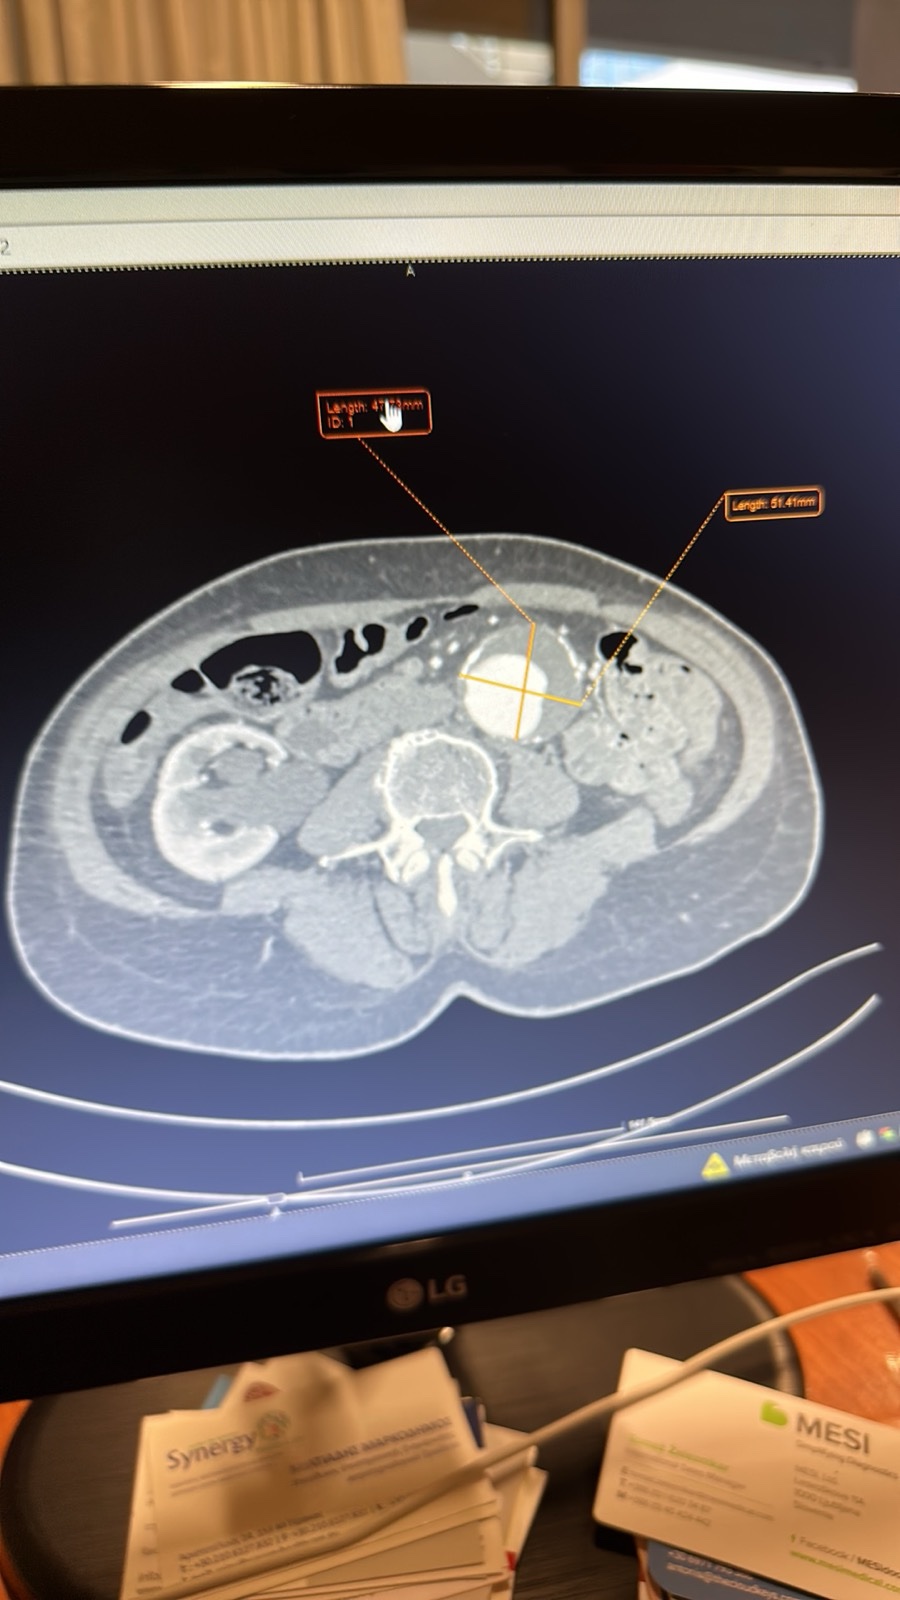

Η διάγνωση του ανευρύσματος κοιλιακής αορτής γίνεται με triplex κοιλιακής αορτής ή αξονική τομογραφία κοιλίας. Κάθε άνθρωπος (στο πλείστο των περιπτώσεων άνδρας) που υπερβαίνει το 60ο έτος της ηλικίας του πρέπει να ελέγχεται με triplex κοιλιακής αορτής (εάν έχει 1ου βαθμού συγγενή με ανεύρυσμα κοιλιακής αορτής η εξέταση πρέπει να γίνει μετά το 50ο έτος). Σε ασθενείς που χρειάζονται αποκατάσταση του ανευρύσματος κοιλιακής αορτής η πιο λεπτομερή προεγχειρητική εξέταση είναι η αξονική αγγειογραφία κοιλιακής αορτής και λαγονίων. Σε ασθενείς που δεν μπορούν να υποβληθούν σε αξονική αγγειογραφία διενεργείται μαγνητική αγγειογραφία κοιλιακής αορτής και λαγονίων.

Η αορτή είναι το μεγαλύτερο αγγείο στο σώμα και μεταφέρει το αίμα από την καρδιά στα υπόλοιπα όργανά. Ως ανεύρυσμα ορίζεται η εστιακή διάταση μιας αρτηρίας τουλάχιστον άνω του 50% της φυσιολογικής διαμέτρου του αγγείου. Επομένως οποιαδήποτε αύξηση της διαμέτρου της κοιλιακής αορτής πάνω από 3 εκατοστά ορίζεται ωςανεύρυσμα κοιλιακής αορτής.

Εάν ένα ανεύρυσμα κοιλιακής αορτής έχει διάμετρο μικρότερη από 5 εκ., έχει μικρή πιθανότητα να υποστεί ρήξη, γι’ αυτό συνιστάται η τακτική παρακολούθηση του ανευρύσματος από αγγειοχειρουργό. Εάν, ωστόσο, ένα ανεύρυσμα είναι μικρότερο από 5 εκατοστά, αλλά αυξάνεται κατά περισσότερο από 1 εκατοστό κάθε χρόνο ή προκαλεί συμπτώματα όπως πόνο στην πλάτη και ευαισθησία, συνίσταται άμεση αποκατάσταση. Εάν το ανεύρυσμά είναι μεγαλύτερο από 5 εκ., θα χρειαστεί αποκατάσταση για την αποτροπή της ρήξης του ανευρύσματος. Η EVAR είναι μια πιθανή θεραπευτική επιλογή.